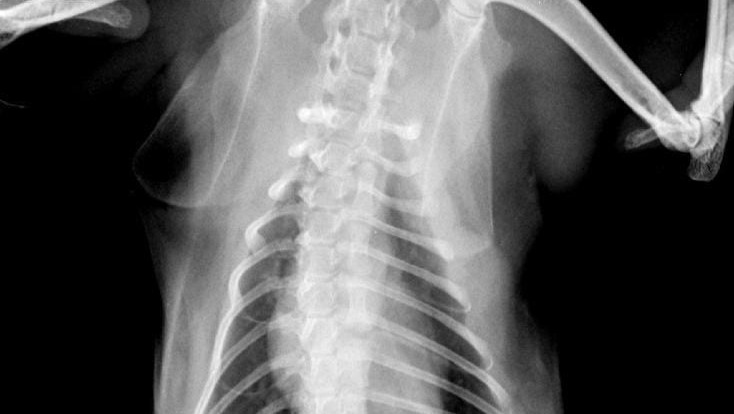

Also, through other tests we found 4 tumors that go from her ear to her jaw which makes it diffivult or painful for her to open it correctly to eat! This masses have to be also removed through surgery and she needs electrochemotherapy on there too, to prevent the carcinoma to keep advancing.

thge next is the diagnose of her ear and jaw. Squamous cell carcinoma grade II and margines grade III.